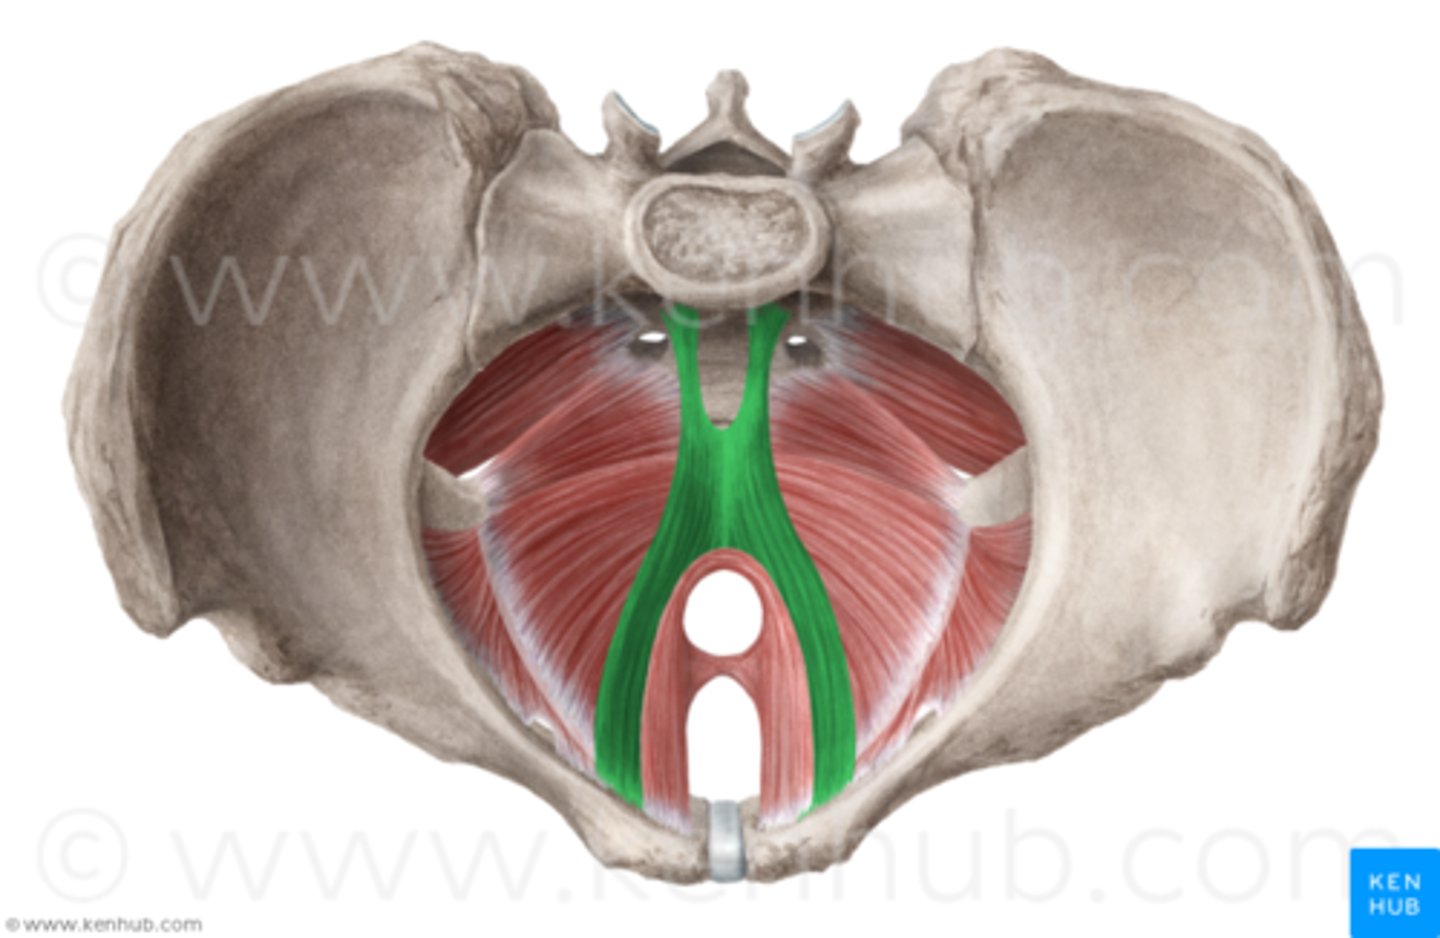

pelvic floor

The muscular base of the abdomen attached to the pelvis, supports pelvic organs, influence urination, defecation, sexual function

levator ani muscles

puborectalis, pubococcygeus, iliococcygeus

urethral canal

lumen of urethra that drains urine from bladder in male and female, and semen from reproductive system in male

hiatuses in pelvic floor

urethral canal, rectal canal, vaginal canal

rectal canal

Most posterior opening in the pelvic floor, bordered by puborectalis

vaginal canal

middle opening in the pelvic floor that allows passage of the fetus during birth

pelvic diaphragm (proper)

levator ani and coccygeus

pelvic diaphragm (all groups)

includes pelvic diaphragm proper, urogenital diaphragm, sphincters and erectile muscles of urogenital tract

Puborectalis

O: anteriorly, from pubic symphysis

I: posteriorly, around anorectal junction

A: inhibits and also aids in defecation, and flatulence

Pubococcygeus

O: pubic bone (lateral to puborectalis)

I: coccyx

A: controls urine flow, contracts during orgasm